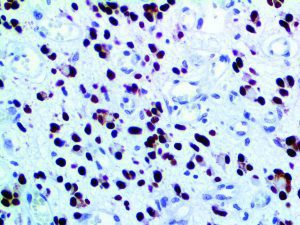

It is the ICU physician who is most likely to witness one of the deadliest manifestations of the abnormal immunological response, the cytokine storm syndrome (CSS). This response is also referred to by some as the cytokine release syndrome (CRS). CSS is characterized by continuous activation and expansion of macrophage and lymphocyte populations, which secrete large amounts of cytokines, causing the cytokine storm. This massive cytokine release is akin to hemophagocytic lymphohistiocytosis (HLH) disease, a syndrome characterized by initial unchecked and persistent activation of cytotoxic T lymphocytes and NK cells.

Clinical and laboratory manifestations of HLH include fever, enlarged liver and/or spleen, neurologic dysfunction, coagulopathy, liver dysfunction, cytopenias (i.e., low levels of erythrocytes, leukocytes, and/or platelets), hypertriglyceridemia, hyperferritinemia, hemophagocytosis, and eventually diminished NK cell activity as the immune system becomes progressively paralyzed. HLH can be familial (primary HLH) or secondary to another disease process (sHLH), such as rheumatic disease, in which it is referred to as macrophage activation syndrome (MAS, characterized by elevated ferritin).